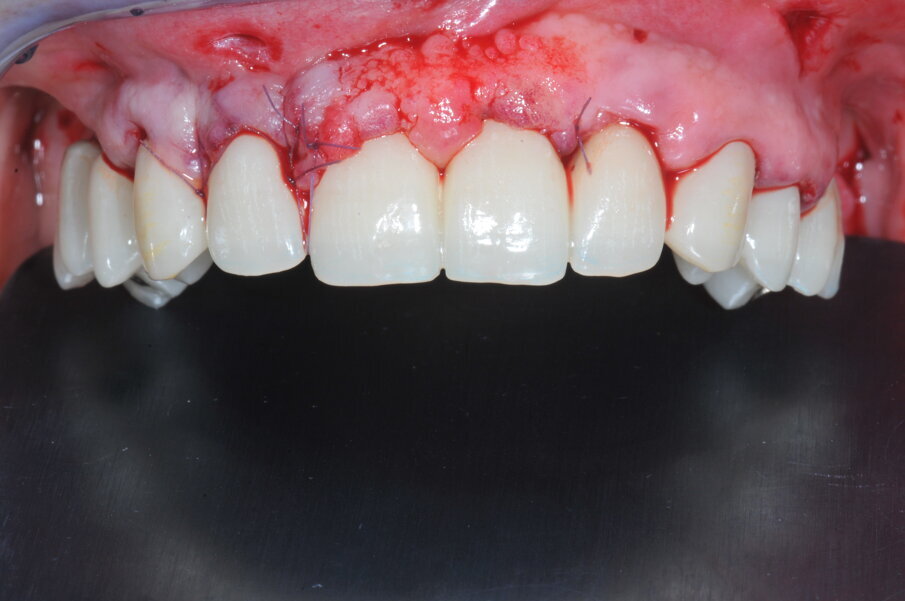

Dopo 4 mesi, è stato necessaria una correzione estetica dei tessuti molli con un ulteriore innesto connettivale bilaminare per migliorare lo spessore dei tessuti molli in area 22 per ottenere un migliore profilo d’emergenza del restauro protesico in corrispondenza dell’area dell’incisivo laterale di sinistra. Dopo il periodo di guarigione per l’osteointegrazione, è stata acquisita una scansione intraorale delle due arcate per replicare i parametri estetici e funzionali determinati per la riabilitazione provvisoria, secondo la tecnica di digital cross-mounting, e per rilevare la posizione degli impianti, utilizzando 4 scan body. I parametri estetici e funzionali sono stati riprodotti dalla protesi provvisoria immediata.

Fig. 4b_Protesi provvisoria a carico immediato.